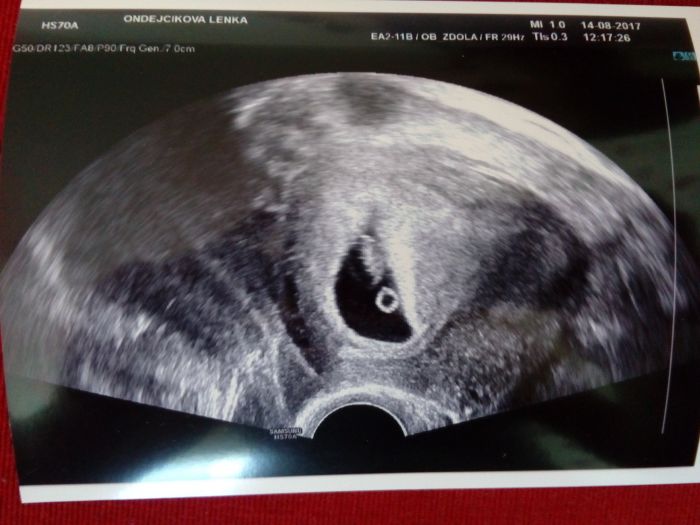

Ahoj holky. Jsem dnes po kontrole. Hrozící potrat snad dá pokoj ;) Jsem 7+4, človíček velký 13mm. Děloha se upravuje do správné pozice. Srdíčko tluče o sto šest :-) Mám velikou radost.

Tak ja taky hlasim, ze jsem konecne po kontrole, dle.uzv 7+0 takze to krasne vychazi podle me ovulace ktera byla 17-18DC. Termin porodu se tedy posunul na 2.4.18.......srdicko nadherne bouchalo, mimco vubec nevypada jak mimco, ale spis jak fazole